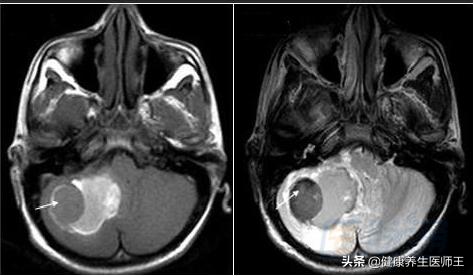

2.MRI和MRA检查 对发现结构异常,明确脑出血的病因很有帮助。MRI对检出脑干和小脑的出血灶和监测脑出血的演进过程优于CT扫描,对急性脑出血诊断不及CT。脑出血时MRI影像变化规律如下:

(1)超急性期(<24小时)为长T1、长T2信号,与脑梗死、水肿不易鉴别。

2)急性期(2-7天)为等T1、短T2信号

3)亚急性期(8天至4周)为短T1、长T2信号

4)慢性期(>4周)为长T1长T2信号